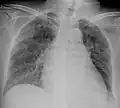

A case of miliary tuberculosis in an 82-year-old woman:

X-ray, 13 days after onset, showing bilateral interstitial infiltrates

X-ray, 22 days after onset, showing extensive bilateral reticulo-nodular infiltrates